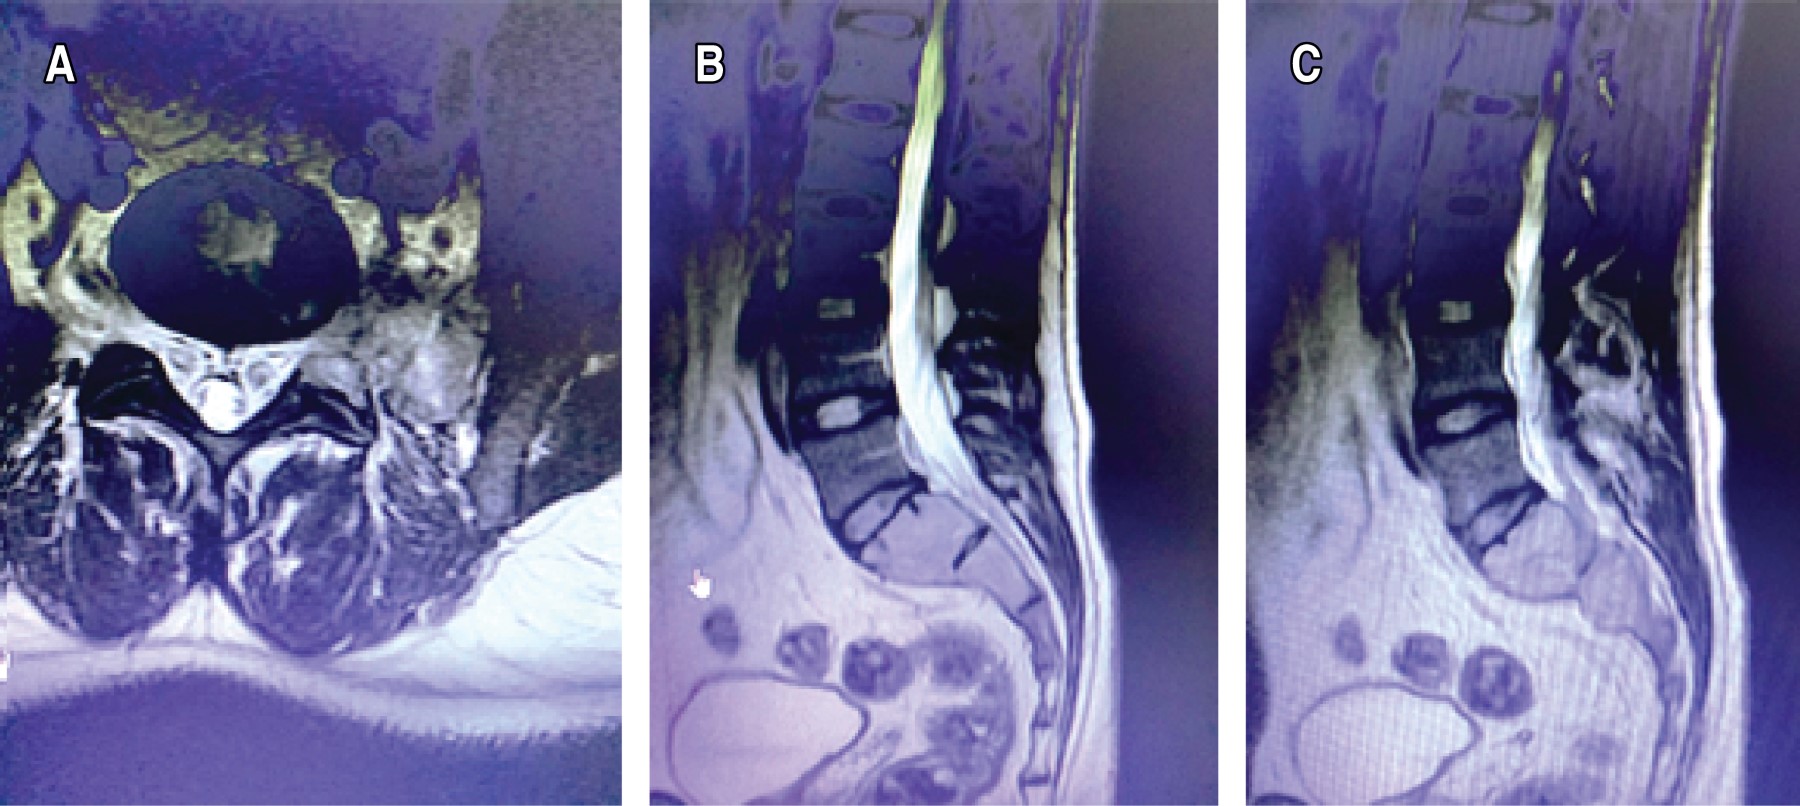

Mujer de 34 años de edad que fue derivada en abril de 2023 a la Unidad Espinal de nuestro hospital, portando tomografía computarizada, con imagen lítica que comprometía todo el sacro, con abombamiento de éste y corticales adelgazadas, pero sin solución de continuidad ni invasión de tejidos adyacentes (Figura 1).10 Clínicamente presentaba dolor lumbar invalidante (escala analógica visual 10/10), sin déficit neurológico, de predominio nocturno, que no cedía con analgésicos ni cambios de posición desde hace un año. Al examen físico presenta dolor a la palpación en región lumbosacro, fuerza muscular M5 y sensibilidad S1 de L5 a distal y bilateral en ambos miembros inferiores; reflejos: rotulianos presentes y simétricos, Babinski y clonus negativos.

La resonancia magnética reveló que la lesión que comprometía el sacro de forma difusa, era hipointensa en la secuencia T1 (Figura 2A), con realce ávido luego de inyectar el medio de contraste intravenoso (Figura 2B) y de forma heterogénea e hipertensa en las secuencias T2 y STIR (Figura 2C y 2D).